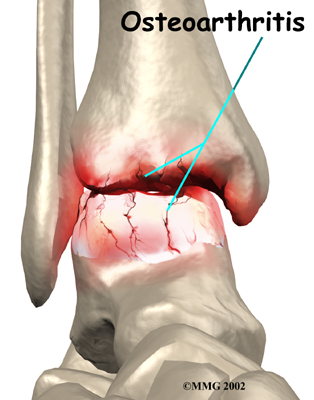

Injury to a joint, such as a bad sprain or fracture, can cause damage to the articular cartilage. The cartilage can be bruised when too much pressure is exerted on it. This damages the cartilage, although if you look at the surface it may not appear to be any different. The injury to the material doesn't show up until months later. Sometimes the cartilage surface is damaged even more severely, and pieces of the cartilage are ripped from the bone. These pieces do not heal back and usually must be removed from the joint surgically. If not, they may float around in the joint, causing the joint to catch and be painful. These fragments of cartilage may also do more damage to the joint surface.

Once this cartilage is ripped away, it does not normally grow back. Unlike bone, holes in the surface are not simply replaced by the cartilage tissue around the hole. Instead the defects are filled with scar tissue. The scar tissue that forms is not nearly as good a material for covering joint surfaces as the cartilage it replaces. It just can't support weight and isn't smooth like true articular cartilage.

An injury to a joint, even if it does not injure the articular cartilage directly, can alter how the joint works. This is true for a fracture where the bone fragments heal differently from the way they were before the break occurred. It is also true when ligaments are damaged that lead to instability in the joint. When an injury results in a change in the way the joint moves, the injury may increase the forces on the articular cartilage. This is similar to any mechanical device or machinery. If the mechanism is out of balance, it wears out faster.

Over many years this imbalance in the joint mechanics can lead to damage to the articular surface. Since articular cartilage cannot heal itself very well, the damage adds up. Finally, the joint is no longer able to compensate for the increasing damage, and it begins to hurt. The damage occurs well before the pain begins.

When OA has reached a very severe stage, the bone itself under the articular cartilage may become worn away. This can lead to increasing deformities around the joint. In the final stages, the alignment of the bones can begin to form odd angles where they meet at the joint.